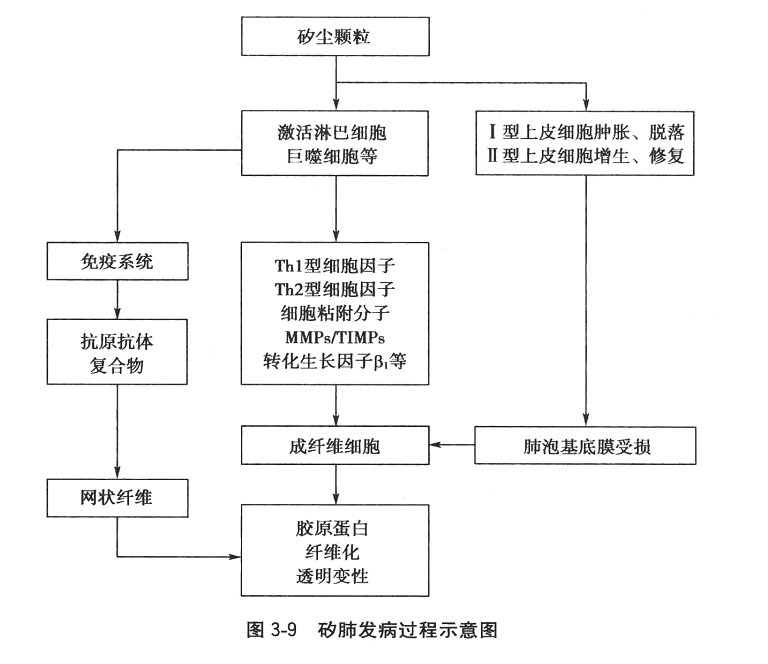

矽肺发病机制十分复杂,且尚未完全阐明,现扼要归纳如图3-9。

三、矽肺发病机制

石英如何引起肺纤维化,学者们提出多种假说,如机械刺激学说、硅酸聚合学说、表面活性学说、免疫学说等。石英尘粒表面羟基活性基团,即硅烷醇基团,可与肺泡巨噬细胞膜构成氢键,产生氢的交换和电子传递,造成细胞膜通透性增高、流动性降低,功能改变;石英直接损害巨噬细胞膜,改变细胞膜通透性,促使细胞外钙离子内流,当其内流超过Ca2+/Mg2+-ATP酶及其他途径排钙能力时,细胞内钙离子浓度升高,也可造成巨噬细胞损伤及功能改变;尘细胞可释放活性氧(ROS),激活白细胞产生活性氧自由基,参与生物膜脂质过氧化反应,引起细胞膜的损伤;肺泡Ⅰ型上皮细胞在矽尘作用下,变性肿胀,脱落,当肺泡Ⅱ型上皮细胞不能及时修补时,基底膜受损,暴露间质,激活成纤维细胞增生;巨噬细胞损伤或凋亡释放脂蛋白等,可成为自身抗原,刺激产生抗体,抗原抗体复合物沉积于胶原纤维上发生透明变性。但这些均不能圆满解释其发病过程。

请看视频:罕见疾病:什么是矽肺病

近年来,矽肺纤维化发病的分子机制研究有了一定的进展。矽尘进入肺内损伤或激活淋巴细胞、上皮细胞、巨噬细胞、成纤维细胞等效应细胞,分泌多种细胞因子等活性分子。尘粒、效应细胞、活性分子等之间相互作用,构成复杂的细胞分子网络,通过多种信号传导途径,激活胞内转录因子,调控肺纤维化进程。这些活性分子包括细胞因子、生长因子、细胞粘附分子、基质金属蛋白酶/组织金属蛋白酶抑制剂(MMPs/TIMPs)等。细胞因子按其作用不同分为Th1型与Th2型细胞因子。Th1型细胞因子IFN-γ和IL-2等在肺损伤早期激活淋巴细胞,主要参与组织炎症反应过程。Th2型细胞因子IL-4、IL-6、IL-10等促进成纤维细胞增生、活化,启动纤维化的进程。CD4+CD25+调节性T淋巴细胞通过细胞-细胞接触和分泌细胞因子IL10、TGF-β1两种方式抑制Th1型细胞因子的产生,调控Th1型向Th2型反应极化的进程。Th2型细胞因子反应在优势时,诱导TGF-β1等分泌增加,TGF-β1促进成纤维细胞增生,通过其信号传导途径调控胶原蛋白等的合成,并抑制胶原蛋白等的降解,形成肺纤维化。